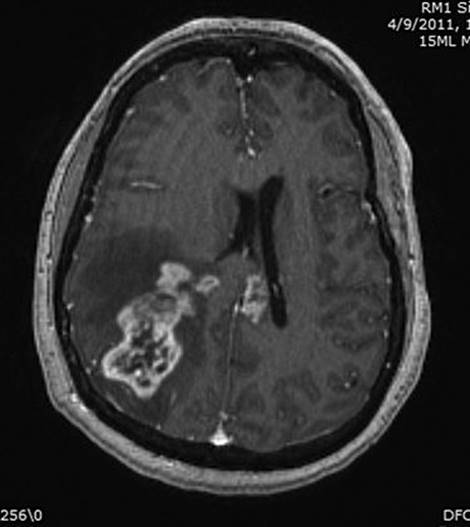

Patients with GBM or AA generally present with a fairly short history of some combination of headache, seizures, and focal neurologic symptoms determined by the tumor location. Malignant gliomas appear on MR scans as an irregular mass lesion with heterogenous or ring enhancement (Fig. 52.1). There is a predilection to extend across the corpus callosum or to spread along other major white matter pathways. T2-weighted or fluid attenuated inversion recovery images typically show abnormal signal extending in an irregular shape for considerable distance beyond the margins of contrast enhancement. In most if not all patients there are infiltrating tumor cells within and beyond the area of abnormal T2/fluid-attenuated inversion recovery (FLAIR) signal. The variable topography and distance of tumor cell infiltration are serious obstacles to attempts at surgical resection or other “focal” therapies for these tumors.

FIGURE 52.1 Axial T1-weighted MRI scan of a patient with a right parietal GBM, showing heterogeneous tumor enhancement, moderate surrounding cerebral edema and associated mass effect, and extension of tumor enhancement across the corpus callosum into the deep left hemisphere.